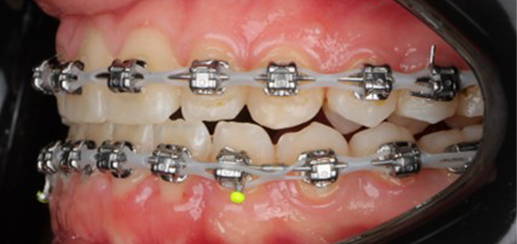

At the end of treatment, the patient’s occlusion was corrected to Class I molar and canine relationships with a physiological overjet and overbite. Irregularities in both arches were eliminated, arch forms were coordinated, and incisor torque was effectively controlled to position the roots centrally within the alveolar bone, enhancing stability. Satisfactory intercuspation was achieved in both the anterior and posterior segments, with maintenance of midline coincidence and periodontal health throughout treatment. The case was finished and transitioned into the retention phase using fixed retainers in the maxillary and mandibular anterior regions.

This case demonstrates that, in the Damon Ultima system, appropriate torque selection provides a rapid and efficient treatment modality, offering enhanced biomechanical control for the clinician and a shorter, more comfortable treatment experience for the patient. In particular, root movements and the finishing phase, which require meticulous management in Class III cases, were completed in a predictable and efficient manner, with high levels of comfort for both the clinician and the patient through the use of carefully selected torque prescriptions.